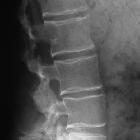

Preschooler

with short stature. Lateral radiograph of the spine shows kyphosis of the thoracolumbar spine and shortened pedicles, posterior scalloping of vertebral bodies and anterior beaking of vertebral bodies.The diagnosis was achondroplasia.